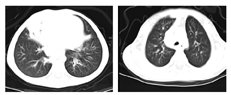

辅助检查:血常规:WBC 8.86×109/L,RBC 4.92×1012/L,PLT 193×109/L,L 1.93×109/L,N 6.36×109/L。血生化正常。过敏源阴性。血沉、降钙素原及CRP均正常。免疫全套:IgG 6.61 g/L,IgA 0.24 g/L,IgM 1.19 g/L,IgE<5 IU/mL,补体C3 0.68 g/L,补体C4 0.16 g/L。T淋巴细胞亚群:总T淋巴细胞数1 191个/μL(正常1 500~2 900个/μL);总B淋巴细胞646个/μL(正常500~1 200个/μL);辅助/诱导性T淋巴细胞(CD4+细胞)565个/μL(正常1 000~2 100个/μL);抑制/细胞毒性T淋巴细胞(CD8+细胞)607个/μL(正常700~1 100个/μL);NK细胞481个/μL(正常300~600个/μL);CD4+/CD8+细胞比值0.93(正常1.1~2.0)。真菌D葡聚糖及曲霉菌抗原阴性。痰培养为流感嗜血杆菌(+)。PPD皮试阴性,结核感染斑点T试验阴性。胸部CT示肺部感染并右肺中叶部分实变;双肺门、纵隔及腋下淋巴结肿大,纵隔点状钙化灶;建议必要时胸部增强CT扫描及结合临床、实验室检查排除特殊感染(结核?)和淋巴瘤(?)(图1)。腹部B超示:肝大;脾大、脾实质回声不均匀;腹腔及腹膜后淋巴结肿大并部分融合;提示结核(?),真菌感染(?),腹腔胀气。入院前支气管镜检查可见各段支气管黏膜弥漫性滤泡样增生,以中下叶及下叶为重(图2)。黏膜活检病理:支气管黏膜上皮脱落、坏死及炎症;上皮细胞表面纤毛结构异常。肺泡灌洗液宏基因检查结果示人类腺病毒C、巨细胞病毒及EB病毒阳性。

诊治经过:患儿在入院后针对痰培养细菌阳性结果予以哌拉西林他唑巴坦抗感染,加强化痰等对症支持治疗,同时辅以支气管肺泡灌洗治疗,予阿昔洛韦治疗,患儿临床症状缓解出院。电话随访患儿服用阿昔洛韦1个月后,2次复查EB病毒阴性。出院后1个月复诊,患儿无咳嗽等不适,结合基因检查结果,最终确诊APDS,建议定期输注丙种球蛋白,家属拒绝用雷帕霉素治疗。最新随访确认,患儿后续前往上海复旦大学附属儿童医学中心就诊后,每月输注丙种球蛋白治疗,已用雷帕霉素半年余,数月来无咳嗽症状,复查肺部CT可见病灶明显吸收。